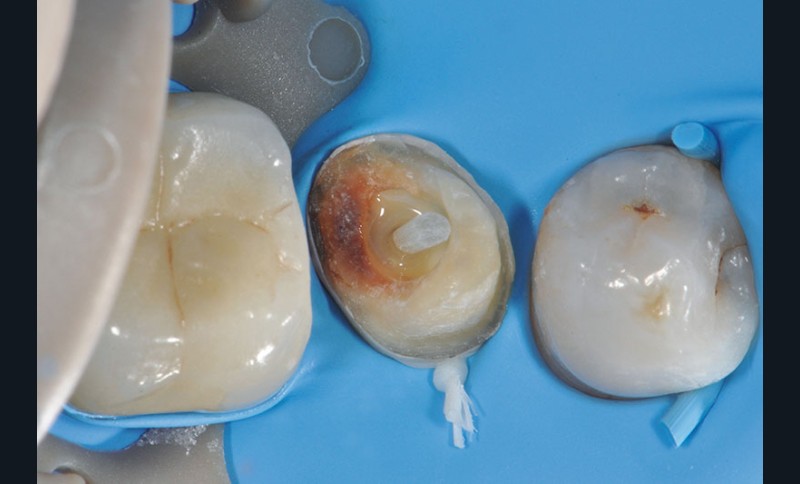

3, 4, 5. La restauration est déposée, les tissus carieux éliminés et la cavité d’accès aménagée avant la réalisation du traitement endodontique. La radiographie postopératoire permet de visualiser l’obturation du canal latéral en regard de la LIPOE.